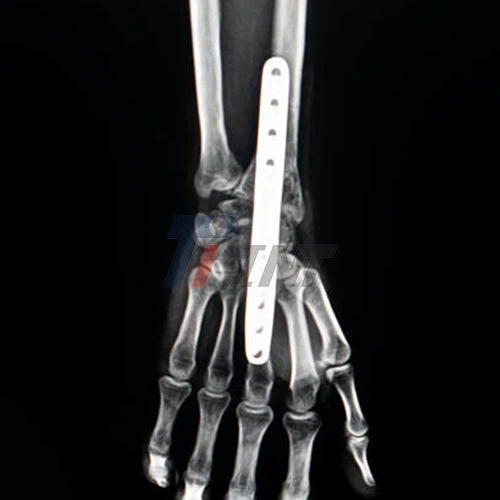

Surgical Procedure and Implantation

The surgical procedure for implanting a titanium plate for a broken wrist typically involves the following steps:

- Anesthesia administration and surgical site preparation

- Incision and exposure of the fractured wrist bones

- Reduction of the fracture to align the bone fragments

- Selection and positioning of the appropriate titanium plate

- Fixation of the plate using titanium screws

- Final adjustments and verification of proper alignment

- Closure of the incision and application of a sterile dressing

The precision and skill of the surgeon, combined with the quality of the titanium plate for broken wrist, are crucial factors in ensuring a successful implantation and optimal fracture fixation.